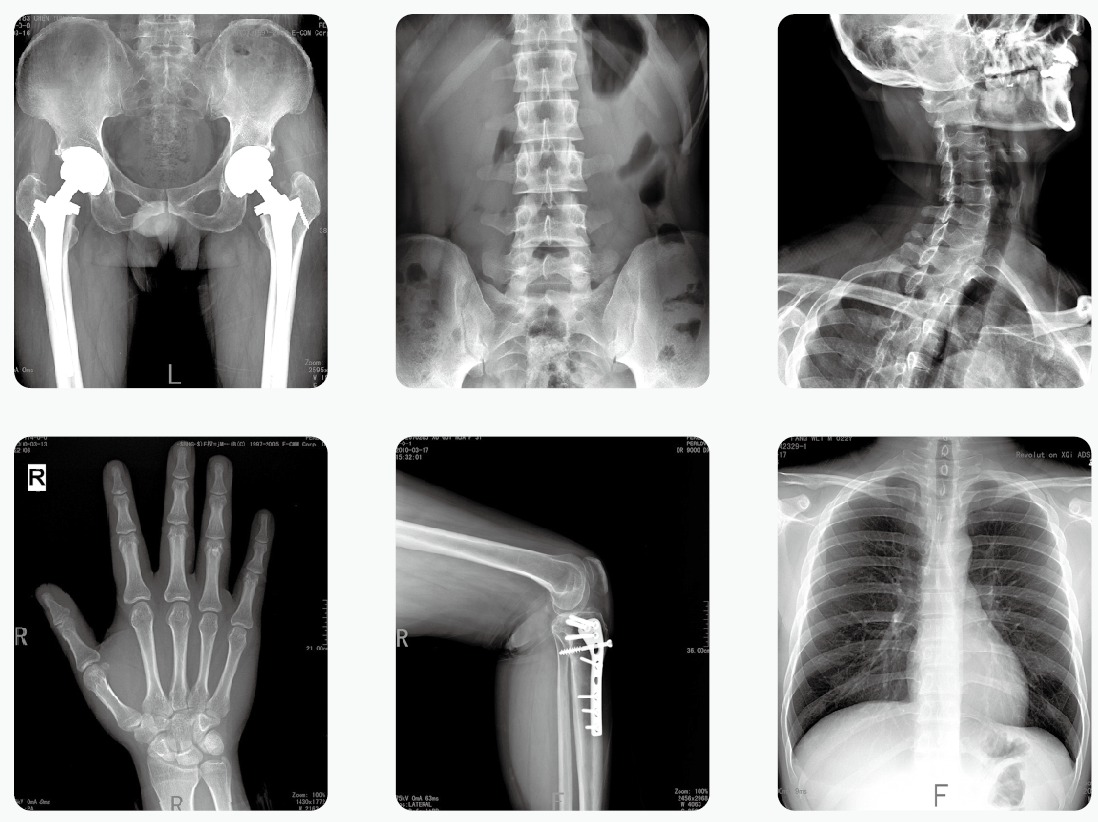

通過醫用X光機檢查,臨床醫生可以獲取病人很多重要的,甚至性命攸關的醫療信息,比如肺炎、骨折、腸梗阻等。這些普通X光檢查,對平常人而言就像是拍數碼照相,咔~可以了。但是對孕婦而言,有時的確是一個艱難的決策。那么,醫用X光機檢查,孕婦到底能不能做?

其實,絕大部分醫用X光機檢查的部位都是四肢、頭、牙齒或者胸部,孕婦的生殖腺并沒有直接暴露在X光下。因此,在這些情況下,只要合理曝光及防護,對胎兒是沒有危害和影響的。

但是,如果孕婦需要做腹部、盆腔、腰椎等醫用X光機檢查,此時胎兒是直接暴露在X光下的,這種情況就需要與醫生探討X光檢查的利弊后再做決定。